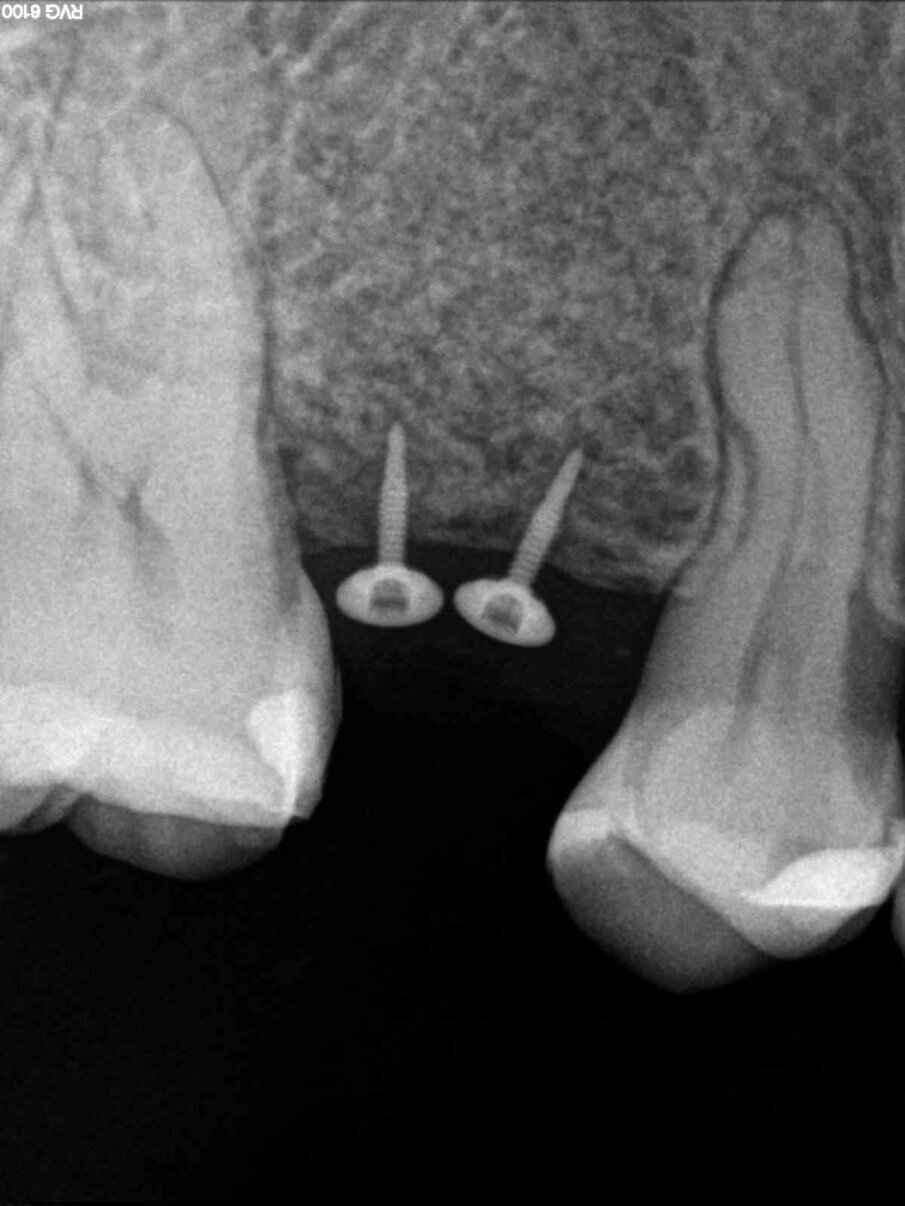

Dopo aver passivizzato il lembo si esegue una sutura a materassaio orizzontale e punto staccato centrale sulla parte crestale e suture semplici sulle incisioni di scarico (Figg. 13, 14). Dopo 10 mesi di guarigione si può procedere all’intervento di posizionamento implantare (Figg. 15-17). Sia dalle fotografie a lembo aperto (Figg. 18, 19) e da quelle di confronto tra la situazione alla baseline e dopo rigenerazione della cresta ossea (Figg. 20, 21) si può valutare come si sia ricostituito un osso ben corticalizzato, vascolarizzato, che ha riempito tutto il difetto osseo preesistente.

Fig. 15 - Controllo radiografico a 10 mesi.